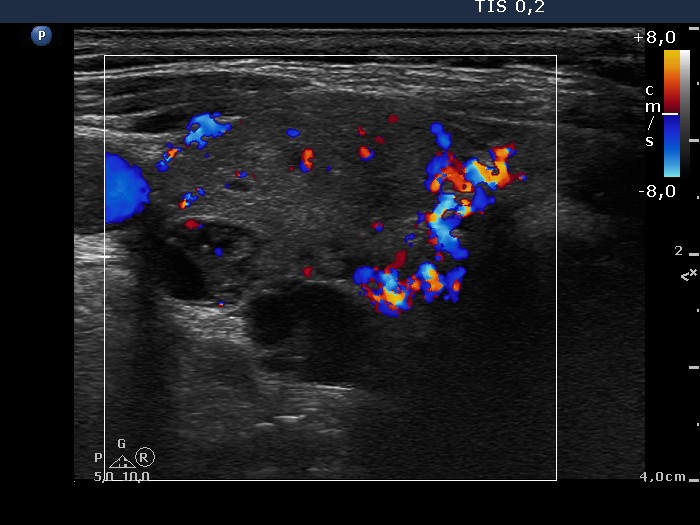

Ultrasonography. The thyroid was composed of multiple nodules with different echogenicities. There was a small hypoechogenic lesion above the right lobe.